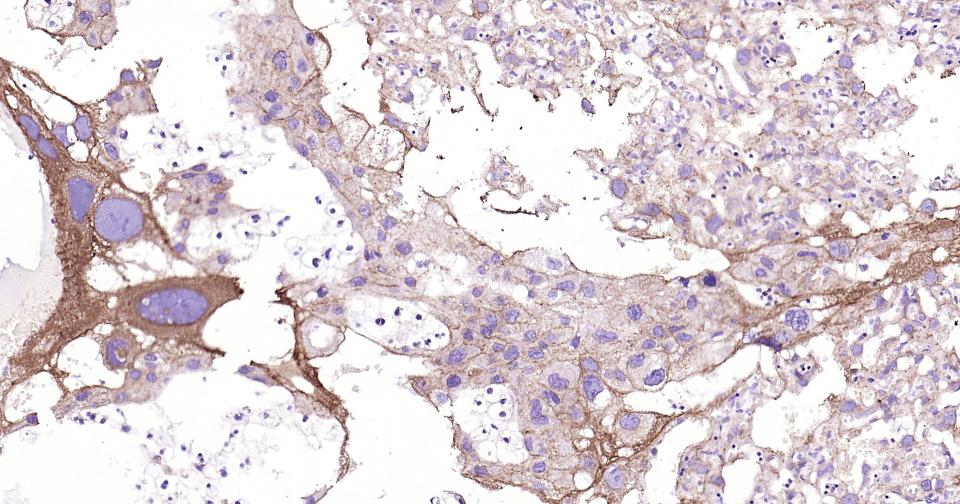

Paraformaldehyde-fixed, paraffin embedded Human Placenta; Antigen retrieval by boiling in sodium citrate buffer (pH6.0) for 15 min; Antibody incubation with CYP26A1 Monoclonal Antibody, Unconjugated(bsm-54341R) at 1:200 overnight at 4°C, followed by conjugation to the bs-0295G-HRP and DAB (C-0010) staining.

Paraformaldehyde-fixed, paraffin embedded Human Colon; Antigen retrieval by boiling in sodium citrate buffer (pH6.0) for 15 min; Antibody incubation with CYP26A1 Monoclonal Antibody, Unconjugated(bsm-54341R) at 1:200 overnight at 4°C, followed by conjugation to the bs-0295G-HRP and DAB (C-0010) staining.

Paraformaldehyde-fixed, paraffin embedded Human Uterus; Antigen retrieval by boiling in sodium citrate buffer (pH6.0) for 15 min; Antibody incubation with CYP26A1 Monoclonal Antibody, Unconjugated(bsm-54341R) at 1:200 overnight at 4°C, followed by conjugation to the bs-0295G-HRP and DAB (C-0010) staining.

Paraformaldehyde-fixed, paraffin embedded Human Liver; Antigen retrieval by boiling in sodium citrate buffer (pH6.0) for 15 min; Antibody incubation with CYP26A1 Monoclonal Antibody, Unconjugated(bsm-54341R) at 1:200 overnight at 4°C, followed by conjugation to the bs-0295G-HRP and DAB (C-0010) staining.

Paraformaldehyde-fixed, paraffin embedded Rat Liver; Antigen retrieval by boiling in sodium citrate buffer (pH6.0) for 15 min; Antibody incubation with CYP26A1 Monoclonal Antibody, Unconjugated(bsm-54341R) at 1:200 overnight at 4°C, followed by conjugation to the bs-0295G-HRP and DAB (C-0010) staining.

Paraformaldehyde-fixed, paraffin embedded Human Pancreas; Antigen retrieval by boiling in sodium citrate buffer (pH6.0) for 15 min; Antibody incubation with CYP26A1 Monoclonal Antibody, Unconjugated(bsm-54341R) at 1:200 overnight at 4°C, followed by conjugation to the bs-0295G-HRP and DAB (C-0010) staining.

Paraformaldehyde-fixed, paraffin embedded Rat Pancreas; Antigen retrieval by boiling in sodium citrate buffer (pH6.0) for 15 min; Antibody incubation with CYP26A1 Monoclonal Antibody, Unconjugated(bsm-54341R) at 1:200 overnight at 4°C, followed by conjugation to the bs-0295G-HRP and DAB (C-0010) staining.

Paraformaldehyde-fixed, paraffin embedded Mouse Pancreas; Antigen retrieval by boiling in sodium citrate buffer (pH6.0) for 15 min; Antibody incubation with CYP26A1 Monoclonal Antibody, Unconjugated(bsm-54341R) at 1:200 overnight at 4°C, followed by conjugation to the bs-0295G-HRP and DAB (C-0010) staining.

Paraformaldehyde-fixed, paraffin embedded Rat Placenta; Antigen retrieval by boiling in sodium citrate buffer (pH6.0) for 15 min; Antibody incubation with CYP26A1 Monoclonal Antibody, Unconjugated(bsm-54341R) at 1:200 overnight at 4°C, followed by conjugation to the bs-0295G-HRP and DAB (C-0010) staining.

Paraformaldehyde-fixed, paraffin embedded Mouse Placenta; Antigen retrieval by boiling in sodium citrate buffer (pH6.0) for 15 min; Antibody incubation with CYP26A1 Monoclonal Antibody, Unconjugated(bsm-54341R) at 1:200 overnight at 4°C, followed by conjugation to the bs-0295G-HRP and DAB (C-0010) staining.

Paraformaldehyde-fixed, paraffin embedded Rat Colon; Antigen retrieval by boiling in sodium citrate buffer (pH6.0) for 15 min; Antibody incubation with CYP26A1 Monoclonal Antibody, Unconjugated(bsm-54341R) at 1:200 overnight at 4°C, followed by conjugation to the bs-0295G-HRP and DAB (C-0010) staining.

Paraformaldehyde-fixed, paraffin embedded Mouse Colon; Antigen retrieval by boiling in sodium citrate buffer (pH6.0) for 15 min; Antibody incubation with CYP26A1 Monoclonal Antibody, Unconjugated(bsm-54341R) at 1:200 overnight at 4°C, followed by conjugation to the bs-0295G-HRP and DAB (C-0010) staining.

Paraformaldehyde-fixed, paraffin embedded (human liver carcinoma); Antigen retrieval by boiling in sodium citrate buffer (pH6.0) for 15min; Block endogenous peroxidase by 3% hydrogen peroxide for 20 minutes; Blocking buffer (normal goat serum) at 37°C for 30min; Antibody incubation with (CYP26A1) Monoclonal Antibody, Unconjugated (bsm-54341R) at 1:200 overnight at 4°C, followed by operating according to SP Kit(Rabbit) (sp-0023) instructionsand DAB staining.